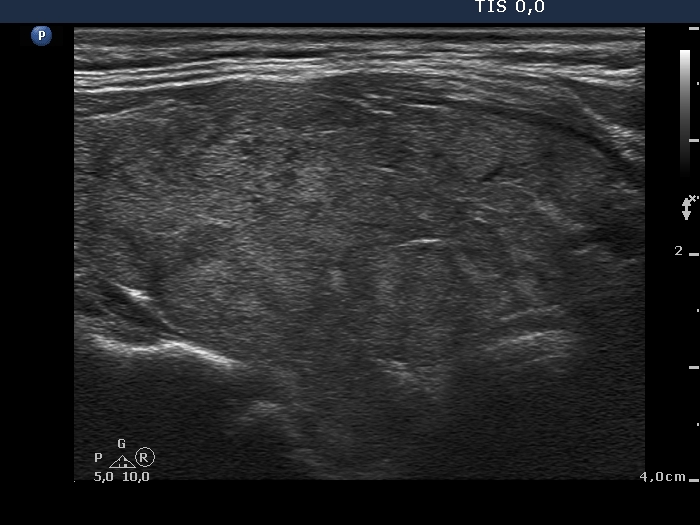

Second examination 6 years later (second row of images):

Clinical data: The patient was referred for a follow-up.

Palpation: unchanged.

Laboratory tests: TSH 3.52 mIU/L.

Ultrasonography. The pattern was the same as in the previous study except for the lesion in the isthmus which has been increased in size.

Suggestion: TSH in a year, ultrasound in 3 years.

Comment. This is the typical presentation of the micronodular form of Hashimoto's thyroiditis.